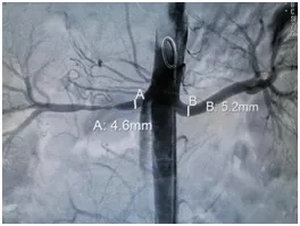

肾动脉DSA检查:右肾串珠样狭窄

右肾动脉支架后管腔通畅

患者确诊以后介入科刘凯医生给予肾动脉支架置入术,术后即刻血压恢复良好,3个月后复查肾脏大小恢复正常。